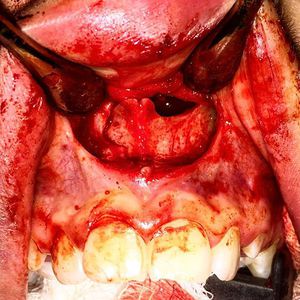

Teeth, cysts, lumps and bumps, no matter what the finding, it's never a boring day in clinic. Maxillofacial anomalies never cease to amaze me. This is a transoral approach to extract a supernumerary tooth that was erupting into the nasal floor. Definitely a different kind of nosejob ๐ช๐๐ค